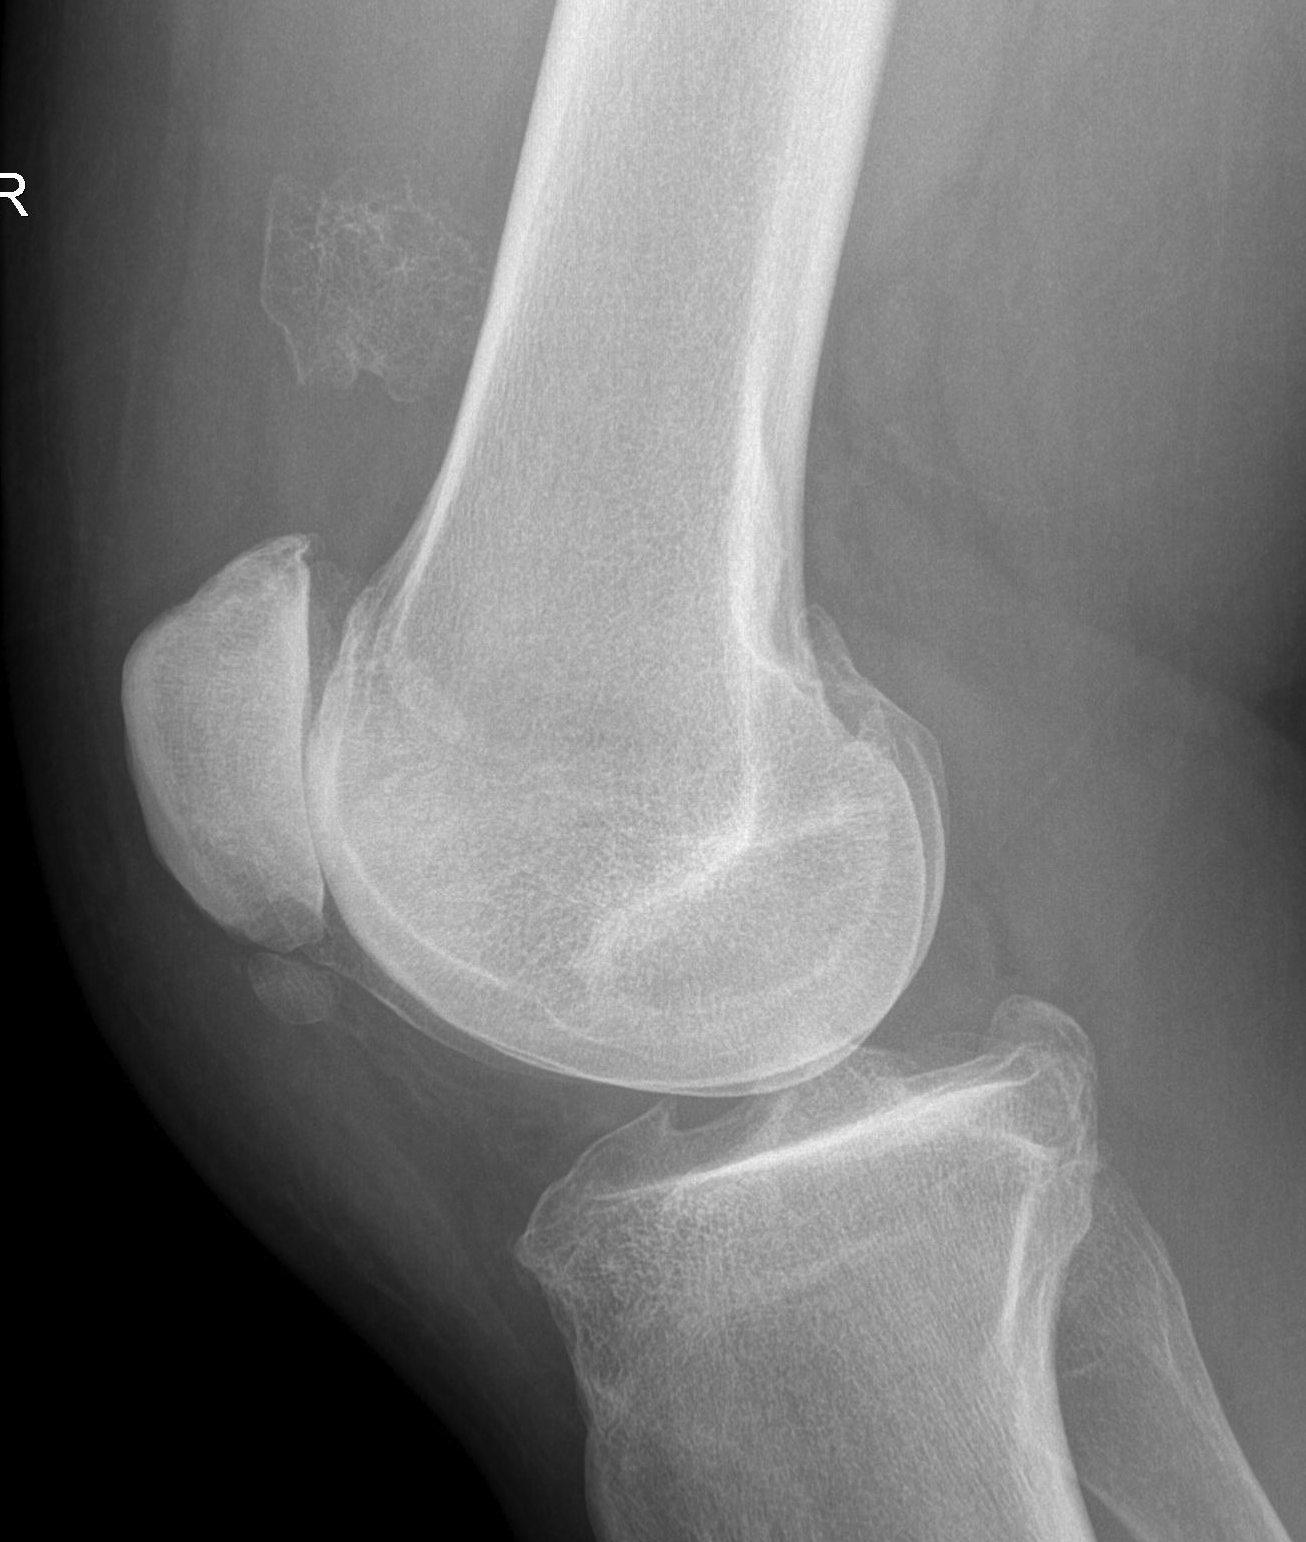

Trauma

- elbow fracture / dislocation

X-ray

Changes occur 2-4 / 52 after injury

Initial cotton candy appearance

- then osseous in appearance

- not attached to bone

- can be resorbed

Mature bone peripherally

DDx

Osteosarcoma

STS

Hemangioma

MO

- diaphyseal (OS metaphyseal)

- intact cortex (OS fractures)

- mature bone peripheral with central fibrous tissue (OS mature centrally)

- pain and swelling improves with time (OS worsens)

- normal osteoblast on biopsy